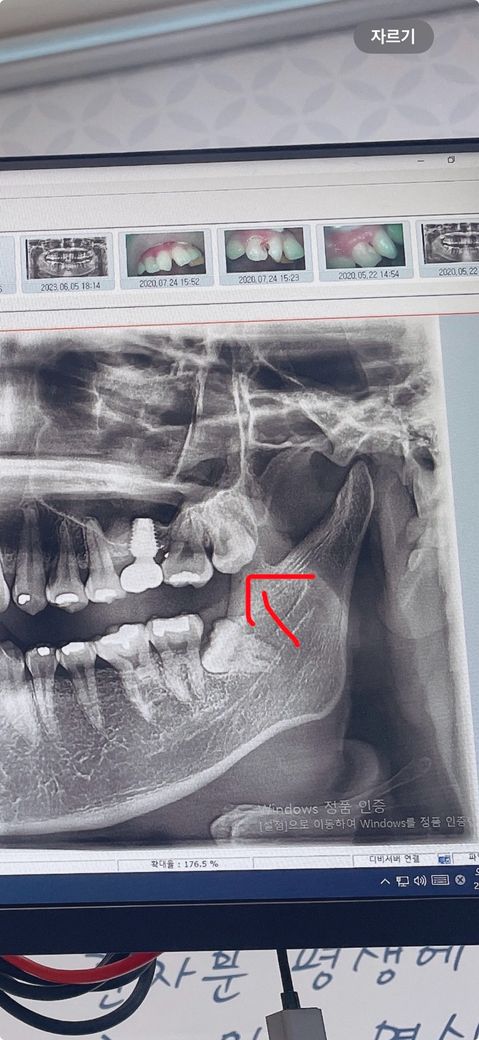

사랑니 엑스레이만 보고 발치 난이도 알수있나요??

동그라미 친게 이번에 발치할 사랑니 인데요 이런경우엔 한번에 뽑히나요? 아님 부셔야 되나요? 난이도가 어떨가요?? 사랑니 발치가 처음이라서요 임플란트때 치아 발치하는거랑 비슷할까요??

사진에 보이는 위쪽 사랑니는 크게 어려운 난이도는 아닌거 같고 단순발치라 쉽게 나올것같습니다.

사진ㅡ로 봤을 때에는 치아는 여러개로 분할하여 발치해야하며 매복깊이가 깊어 어렵습니다.

윗쪽 사랑니 화살표가 가리키는 치아 즉 사랑니 입니다. 사랑니 중간부위가 썩어있는 발치하는 도중 부러질 가능성도 있습니다. 부러지지 않으면 한덩어리로 뽑을 수도 있습니다.

1. 네 통상적으로 입 안 검사하고, 파노라마 엑스레이로 난이도 평가합니다

2. 단순 발치로 어렵지 않게 가능할 것 같습니다